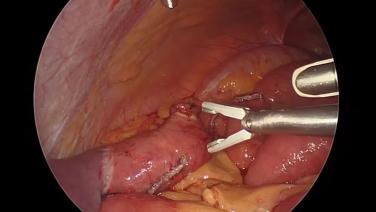

Gastric Bypass with the ECHELON 3000 stapler

Gastric Bypass Revision with the ECHELON 3000 stapler

Roux-en-Y Gastric Bypass Using the HARMONIC™ 1100 Shears and ECHELON™ Flex ENDOPATH™ Stapler with Kelvin Higa, MD

ECHELON 3000 Stapler in Bariatric Procedures with Michael Snyder, MD